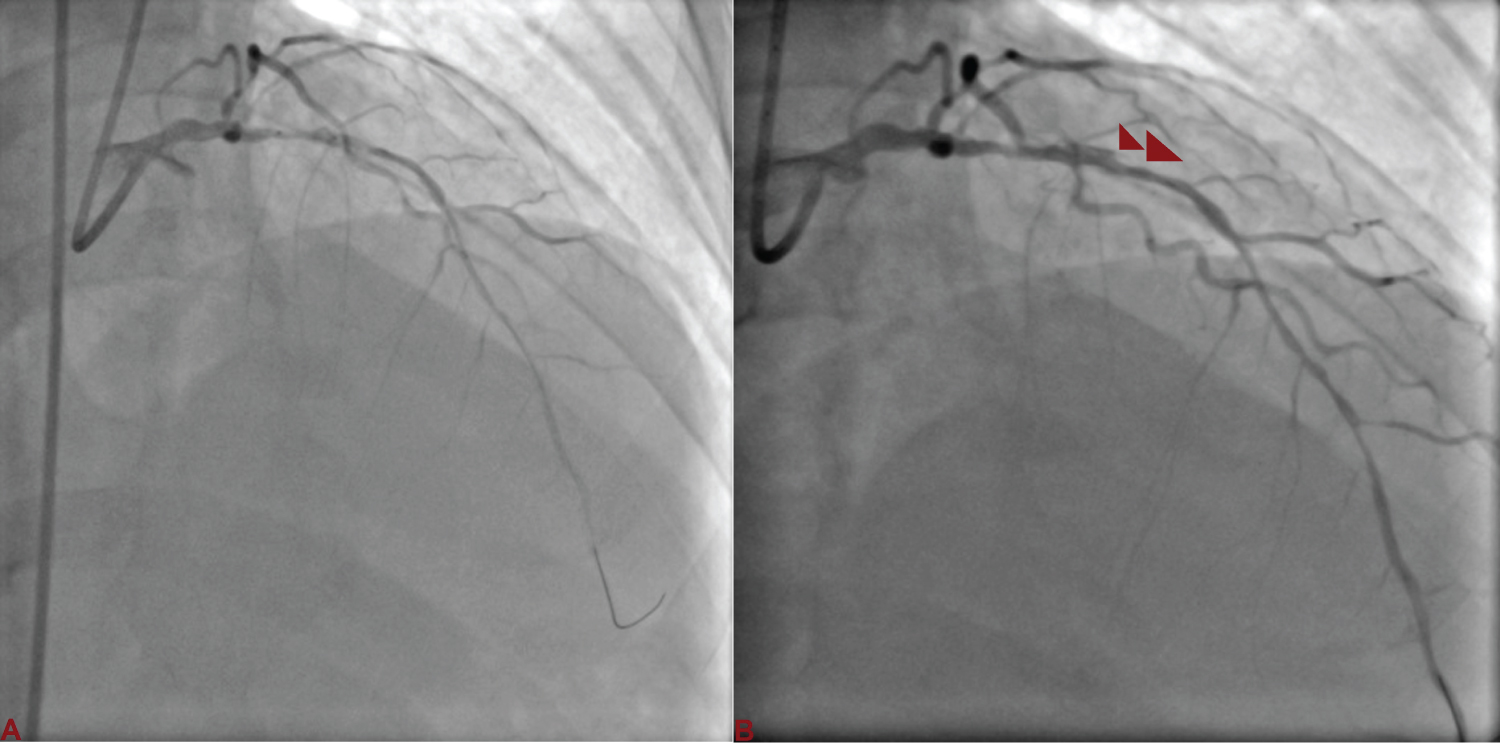

A 76-year-old male, smoker and hypertensive presented with chronic stable angina- Canadian Cardiovascular Society (CCS) class III. Coronary angiography was performed after proper consent which revealed diffuse disease of proximal left anterior descending artery (LAD) with significant stenosis. Aortic sinus was little dilated, so little difficulty was encountered in cannulating left main with Judkins left (JL) guiding catheter. Lesion was wired with runthrough (Terumo, Japan) and sequentially dilated with 1.5 × 10 and 2 × 10 mm Sapphire semicompliant balloon (Orbus Neisch, Netherland) (Figure 1A). After balloon dilatation, dissection at the distal edge was noticed (Figure 1B). As stent could not be tracked and pushed along the lesion as guide catheter used to back out, it was decided disease to change the guide catheter to extra backup (EBU) guide catheter. We could not pass the wire across the lesion and park it distally. Patient started complaining of chest pain. On contrast injection, our wire was seen into the false lumen along with a long segment spiral dissection spreading downward (Figure 2A) and the left circumflex artery was not visible (Figure 2B). It was inferred that spiral dissection was spreading bi-directionally. Keeping runthrough wire there, Sion black (Ashahi, Japan) was tried to be parked into true lumen using parallel wire technique. Once Sion wire was in true lumen distally, runthrough wire was pulled out. It was decided to seal the dissection first. 2.75 × 38 mm Xience Prime everolimus eluting stent (Abott Vasc, USA) was deployed at 12 atm pressure to seal the flap (Figure 3A and Figure 3B). LCx was carefully wired using Sion wire, and dilated with 1.5 × 10 mm Sapphire balloon restoring the flow (Figure 4A). It was stented with 2.75 × 23 mm Xience Prime stent at 12 atm pressure, thereby sealing the dissection and restoring LCx (Figure 4B and Figure 4C). Sion wire in LAD was carefully manuvoured and parked distally into true lumen (Figure 5A, Figure 5B and Figure 5C). The dissection flap was still visible starting from the distal edge of the deployed stent. Another 2.5 × 28 mm Xience Prime stent was deployed overlapping with proximal stent (Figure 6A). The Stent was post dilated by 2.75 × 10 mm Sapphire non-compliant (NC) balloon. Both the LAD and LCx started showing TIMI III flow after stenting with complete sealing of dissection flap (Figure 6B). He was discharged in stable condition with prasugrel 10 mg, aspirin-75 mg, rosuvastatin- 40 mg, metoprolol-100 mg, and ramipril-10 mg.

Figure 1: A) Left anterior descending artery (LAD) was wired with runthrough and sequentially dilated with 1.5 × 10 and 2 × 10 mm semicompliant balloon; B) Dissection (red arrowhead) at the distal edge following balloon dilatation. View Figure 1